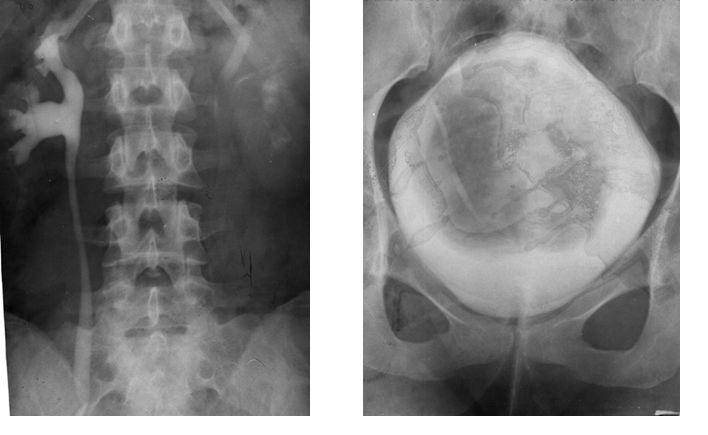

Cistograma Fracturi ale ambelor

ramuri pubiene

Contur neregulat al vezicii urinare Disjunctie

sacro-iliaca dreapta

Hematom pelvian